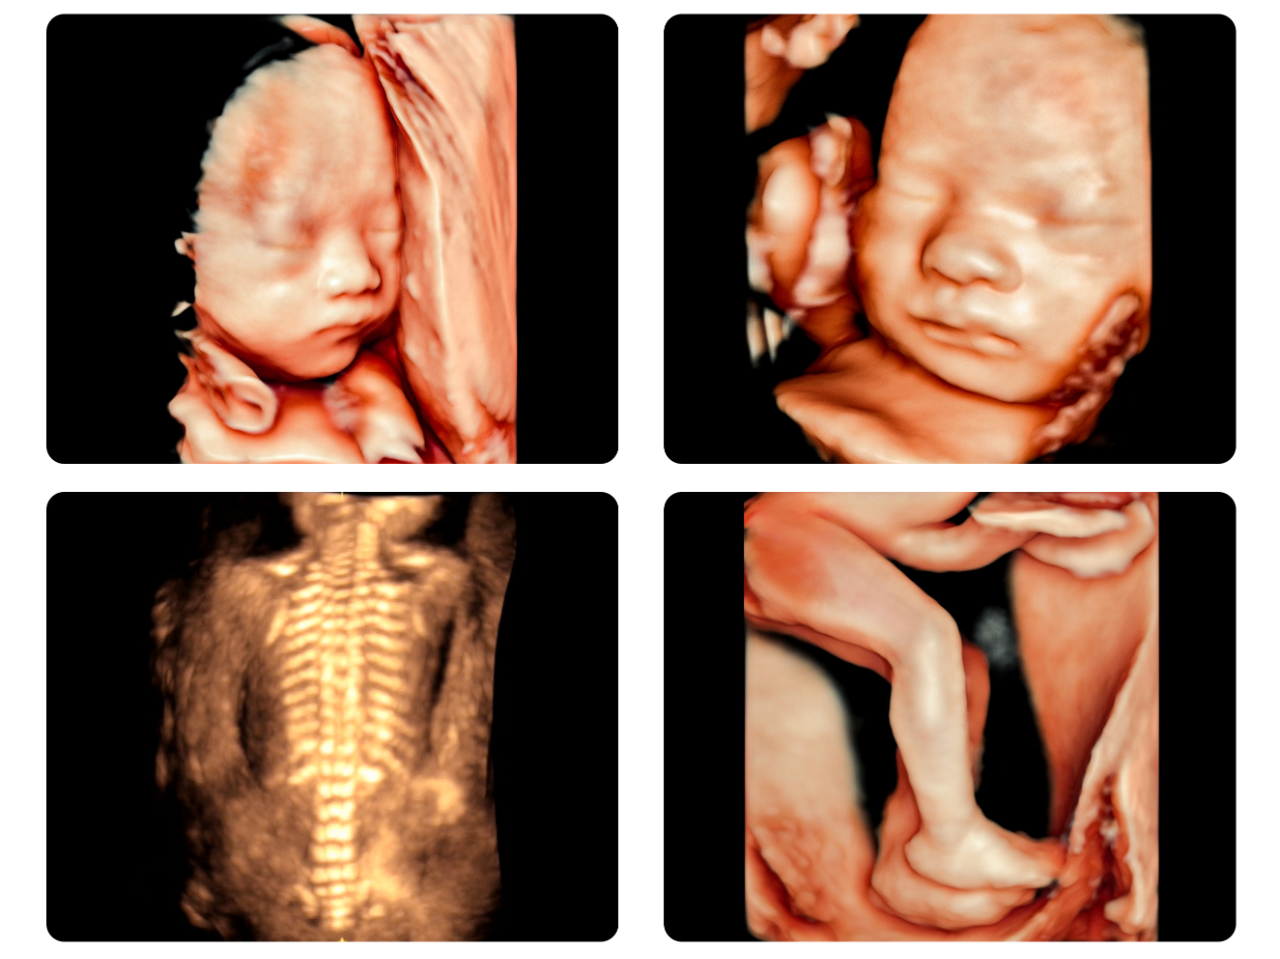

△美国GE高清四维彩超实机拍摄△

哇~谁家的宝贝在揉眼睛、打哈欠?

哈~肉嘟嘟的小手和小脚丫,萌到心里去了~

哇塞!这么清楚又可爱的四维照片哪里拍啊?